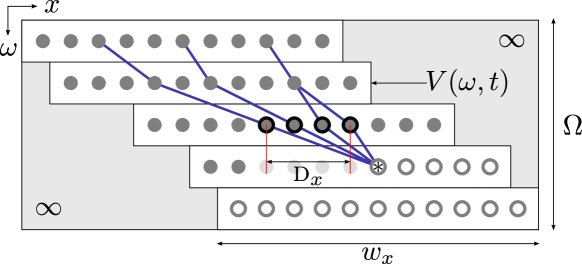

In this step, at a given time , the ensemble of 1D similarity vectors , resulting from the raw motion estimation of the points , are considered collectively. A combinatorial analysis is performed to determine, among all possible solutions describing the displacement of the ensemble of all points, the optimal motion field given the following rules: i) data similarity: displacement is guided by the SSD matching criterion represented by the 1D similarity vectors , ii) non-crossing trajectories: the initial ordering of the points along the axis does not change, iii) motion smoothness: increase or decrease of the -wise distance between two neighboring points is penalized, and iv) motion uniformity: between two successive frames, all moving points must either follow a displacement towards the right or left side of the image. The implementation enforcing these rules is described below.

A dynamic programming algorithm based on front propagation is proposed. A cost function is constructed in the artificial space , where each 1D similarity vector is oriented along the direction and centered on (Figure 3f). Here, the axis of the coordinate system corresponds to the left-to-right ranking of the points: two neighbors points and yield . The values of outside of the region covered by the maps correspond to non-reachable positions, and are therefore set to infinity.

The condition of motion uniformity is addressed by using to generate two cost functions (Figure 3g). In each row of (respectively, ), the value of the points whose -coordinates are strictly smaller (respectively, larger) than is set to infinity, thus enforcing a global displacement to the right (respectively, left).

A front propagation is then run to build two cumulative cost functions and . For , is initialized with the corresponding values of . Then, for , is iteratively generated according to Equation 2.

| (2) |

To provide a more intuitive grasp of this relation, the cumulated cost of the current node (first line, left part) is determined as the minimal value, across a reachable neighborhood , of the addition of i) the cumulated cost of the previous node (first line, right part), and ii) the sum of the cost of the current and previous nodes (second line) multiplied by a factor to penalize non-realistic distances between the two nodes (third line). Here, prevents crossing point trajectories, namely to respect the condition given two points and such that . The elasticity of the mesh is controlled by the smoothing coefficients , , and , as well as by the parameter , which represents the expected -wise distance between two adjacent points, namely one pixel in the original image corresponding to ten pixels in the interpolated image. The distance penalty is null when two neighbors points are separated by exactly ten pixels (one pixel in the non-interpolated image), and gradually becomes greater when the distance between these two points increases (stretching) or decreases (compression). A schematic representation of the front propagation is provided in Figure 4.

Finally, the optimal paths and are extracted in both and via back-tracking zahnd2017fully from the point having the minimal cumulated cost (Figure 3h). The solution with the minimal cost among and is used to determine the motion field such that (Figure 3i).